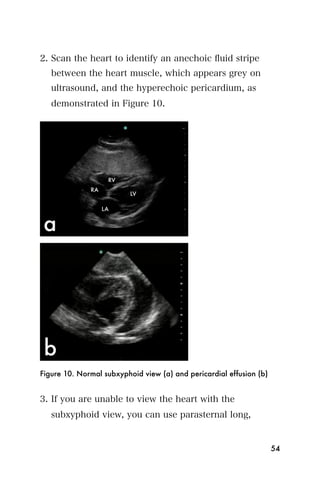

2. Scan the heart to identify an anechoic fluid stripe

between the heart muscle, which appears grey on

ultrasound, and the hyperechoic pericardium, as

demonstrated in Figure 10.

Figure 10. Normal subxyphoid view (a) and pericardial effusion (b)

3. If you are unable to view the heart with the

subxyphoid view, you can use parasternal long,

54

parasternal short or Apical four chamber views to

inspect for pericardial effusion, which will appear as

an anechoic stripe surrounding the hyperechoic

pericardium. See the Echocardiography chapter for

more information.